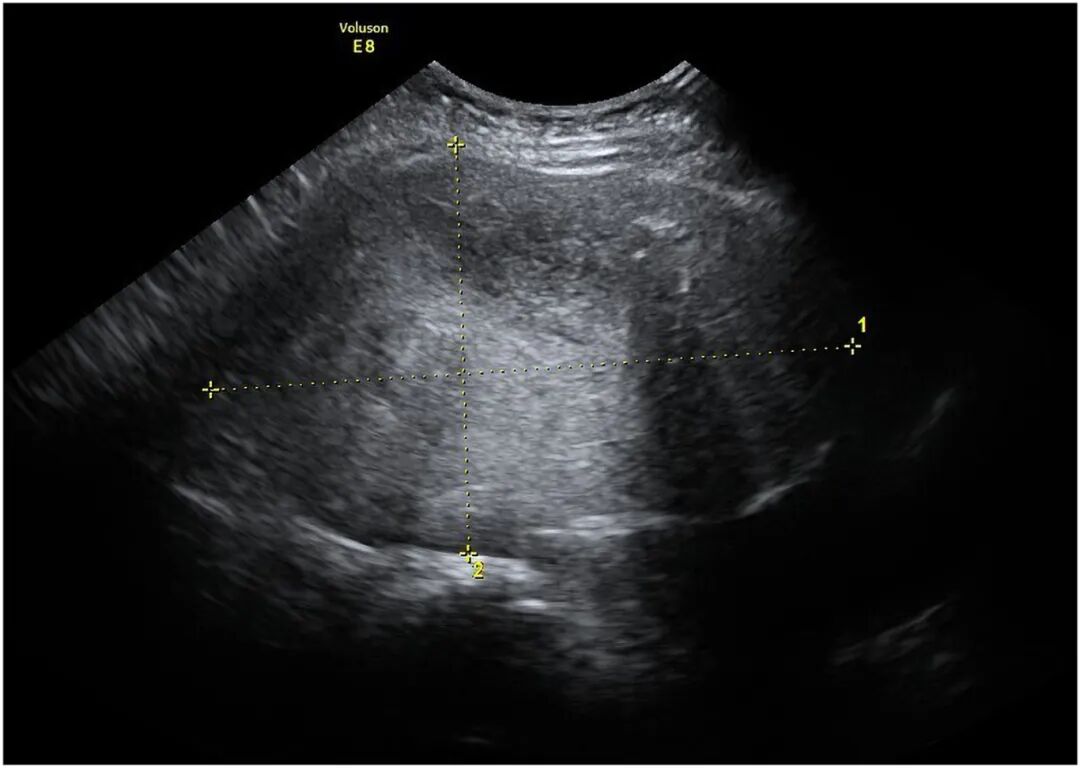

下腹部可触及一压痛性肿块,床旁超声提示一边界清晰的高回声肿块,大小约13cm(图1)。

图1 经腹超声检查示一边界清晰的高回声肿块,大小为13.6 cmx8.6 cm(测量游标所示)。